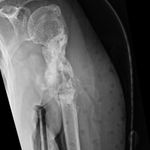

Some time in late May 2010, she presented with movement of the fracture site and was noted that the central area of healing had broken down and was thought that she had a deep infection. She was taken back to theater in mid June 2010 when operation showed that there was no pus. Multiple samples of the fracture site were taken and an external fixator applied with compression of the fragments. Following that, the cultures taken from the wounds showed no growth and no organisms and a biopsy showed no sign of any malignancy or abnormal cells. The fixator became loose and eventually had to be removed. This was done in July 2010 and she was discovered to be going onto a hypertrophic nonunion. Low dose ultrasound treatment of the fracture site was tried to help stimulate healing over the course of a few months but the non union persisted.

She was advised of the need to do some sort of stabilization which is necessary since the use of low-dose ultrasound has not helped in the healing process. She was unwilling to have any further operative intervention and sought further options. Eventually, she agreed to a fourth procedure of intra-medullary nail stabilization of the fracture and had this carried out in April 2011. An intramedullary nail was inserted in an antegrade manner and she has since gone on to heal the fracture site completely and has regained most of the function of the upper limb with no pain.